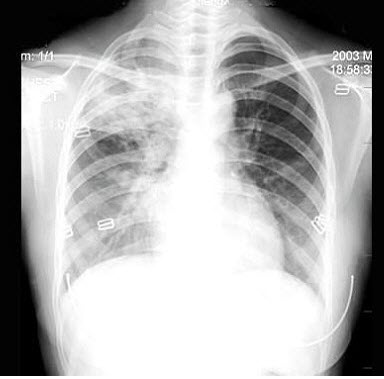

2、单项选择题

男,8岁,高热达38.5℃三天,如图所示,最可能的诊断为()

104、单项选择题

女,26岁,咳嗽发热1周,无胸痛胸闷,X线检查如图,最可能的诊断是()

A.右侧大叶性肺炎

242、单项选择题

男,66岁,近1月来感胸闷,有时低热,胸片如图,最可能的诊断为()

A.化脓性胸膜炎